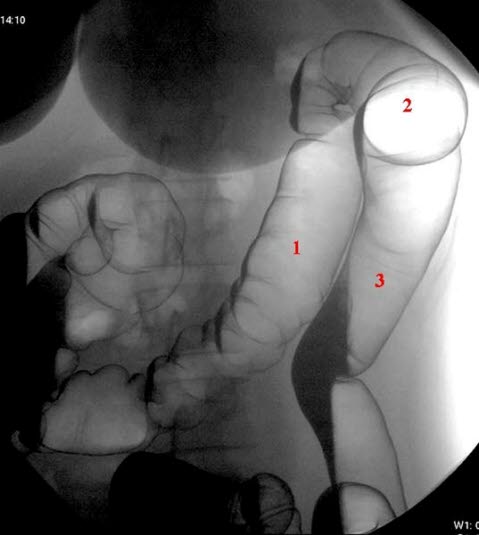

Venstre colonflexur avfotografert med pasient i høyre sideleie

- Colon transversum

- Venstre flexur

- Colon descendens